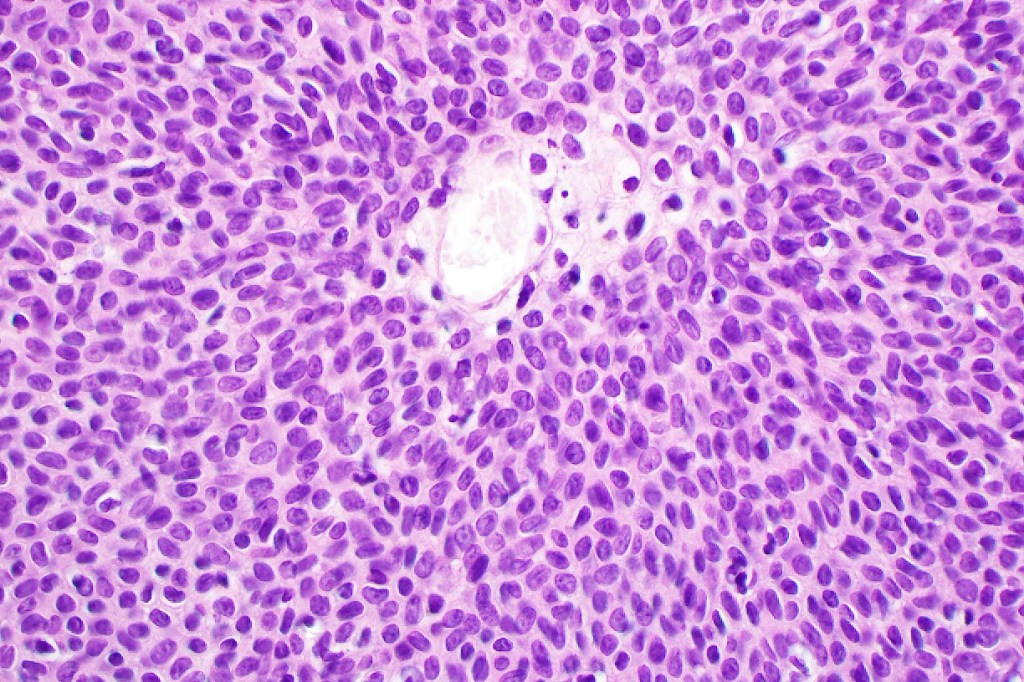

•Careful scrutiny and often levels are required to reveal intracytoplasmic lumina or ductal differentiation

•Dermal duct tumor comprises dermal nodules composed of poroid cells showing ductal differentiation & intracytoplasmic lumina with variable cyst formation